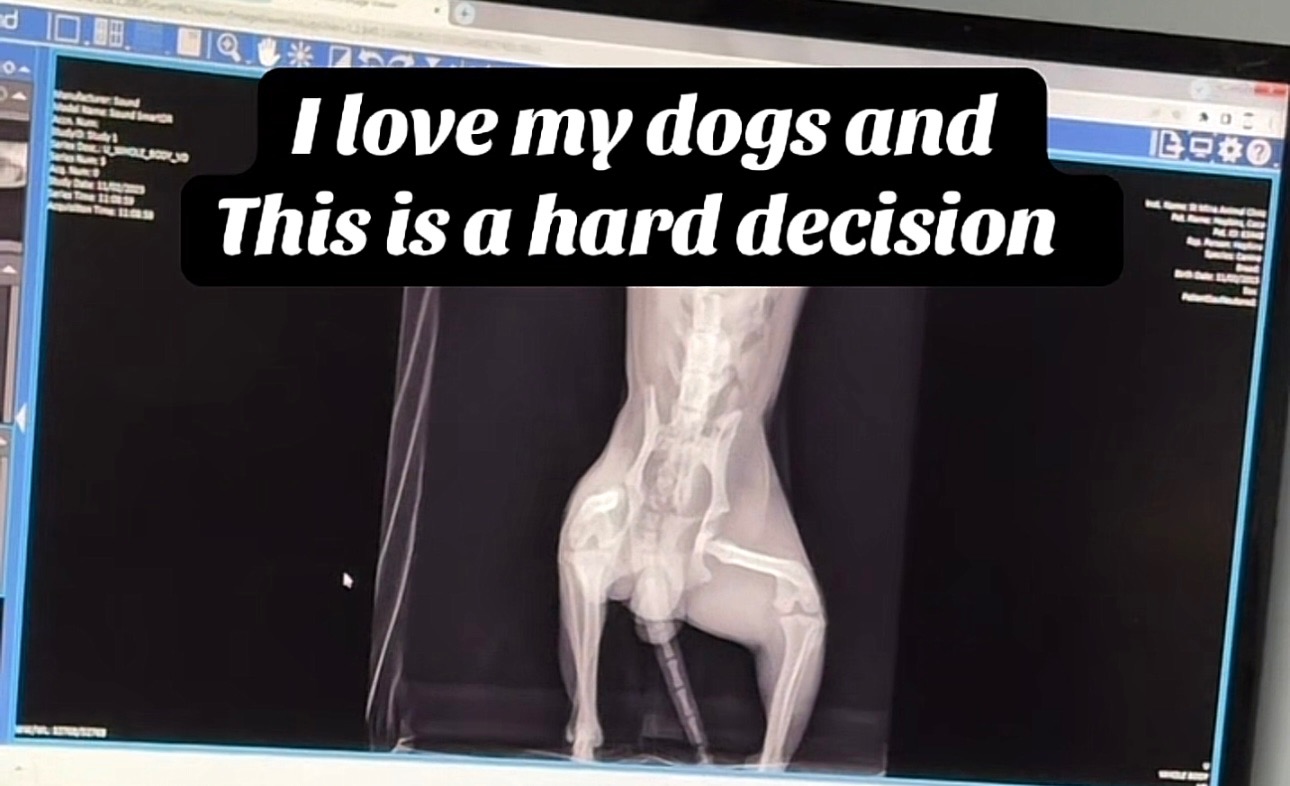

Friday Oct 31,2025 I came home to my mom telling me my dogs were playing as they always do but something is wrong with Koko’s leg. When I took him to the vet , they did x-rays and showed me that now his left hip is dislocated. The coat of the surgery will be $4000. I love my dogs soo much. They are my life. They are my children, my only 2 boys I have. The only 2 children in my household . I have been crying so much because I genuinely can not afford the surgery and I do not have pet insurance. Nor do I want to give my dogs up or put them down. Because they are in perfectly good health despite the last 2 years being ruff for us. Please find it in your heart to donate what ever you can. A little bit goes a long way & we are extremely grateful for whatever we can get to help. Thank you for taking the time out to support and read my story.